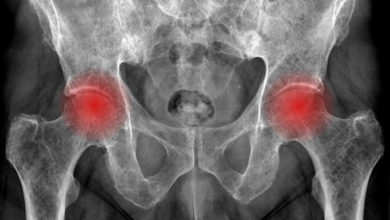

Femur başı avasküler nekrozu

Kalça ekleminin çok önemli bir sorunudur. Erken yaşlarda kalça eklemi artrozuna (kireçlenmesine) neden olabilir. Çok farklı nedenlerle (ilaç kullanımı, başka…